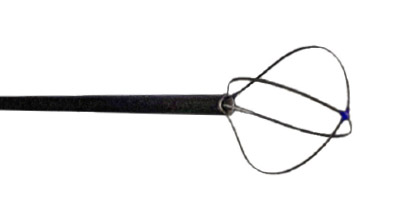

Excellent memory and flexibility

Minimal trauma and Bleeding

With tuohy borst connected, allowing 272μm Fiber to be introduced

| Reference | Description | Ø (Fr) | Wire | Working Length (cm) | Basket Ø (mm) | Basket Length (mm) |

|---|---|---|---|---|---|---|

| ROKP1001ST | PerkX Coaxial PCNL Stone Extractor for Rocamed Laser Fiber max 272μm | 10 | 4 | 38 | 20 | 17.5 |